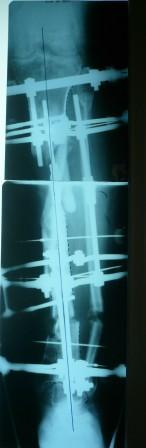

3) Третьим этапом наложили модуль на промежуточный фрагмент.(рис 3)  И начали его транспорт на стержне в проксимальном направлении. (рис 3 а)

Надеемся что <вырастет> регенерат в дистальном отделе, а в проксимальном отделе фрагмент <упрется> и прирастет.

Имя     : Рис 3 Рентг до Начало транспорта фрагмента 6.03.09.JPG

Тип     : image/jpeg

Размер  : 17610 байтов

Описание: отсутствует

Url     : http://weborto.net:8080/pipermail/ortho/attachments/20090405/a3dc024e/attachment-0015.jpeg

Имя     : Рис 3 Рентг до Начало транспорта фрагмента 6.03.09 (1).JPG

Размер  : 17307 байтов

Url     : http://weborto.net:8080/pipermail/ortho/attachments/20090405/a3dc024e/attachment-0016.jpeg

Имя     : рис 3 а.JPG

Размер  : 16419 байтов

Url     : http://weborto.net:8080/pipermail/ortho/attachments/20090405/a3dc024e/attachment-0017.jpeg